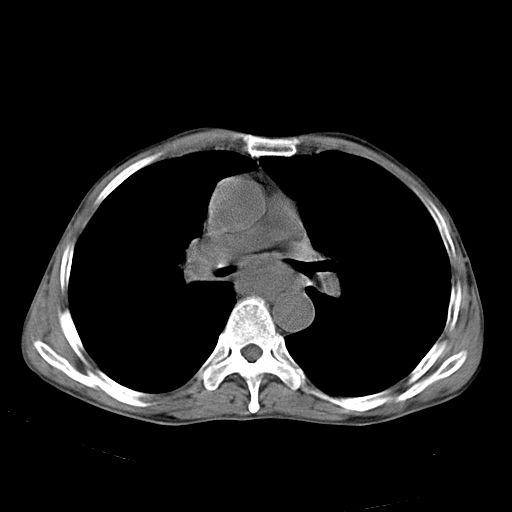

以下是引用苯小孩在2007-5-24 12:47:00的发言:[br]右侧肺门处不均匀密度软组织块影,远端肺组织见斑片模糊影,纵隔内淋巴结明显肿大,边界不清.<纵隔窗第12层面支气管内似见软组织结节>[br]考虑:1、右侧中央性肺癌并阻塞性肺炎并纵隔淋巴结转移可能性大.建议强化或纤支镜进一步检查.[br]2、隆突下淋巴结肿大/食道病变?请做鉴别检查.

以下是引用zhangzhongshou在2007-5-24 12:55:00的发言:[br]1、右肺中叶中心型肺癌并右肺门、隆突下、纵隔淋巴结转移。右肺中叶阻塞性肺炎。

以下是引用jw-830在2007-5-24 15:24:00的发言:[br][br] [br] 考虑右肺中央型肺癌并阻塞性炎症,右肺门及纵隔淋巴结转移。 [br] [br][br]